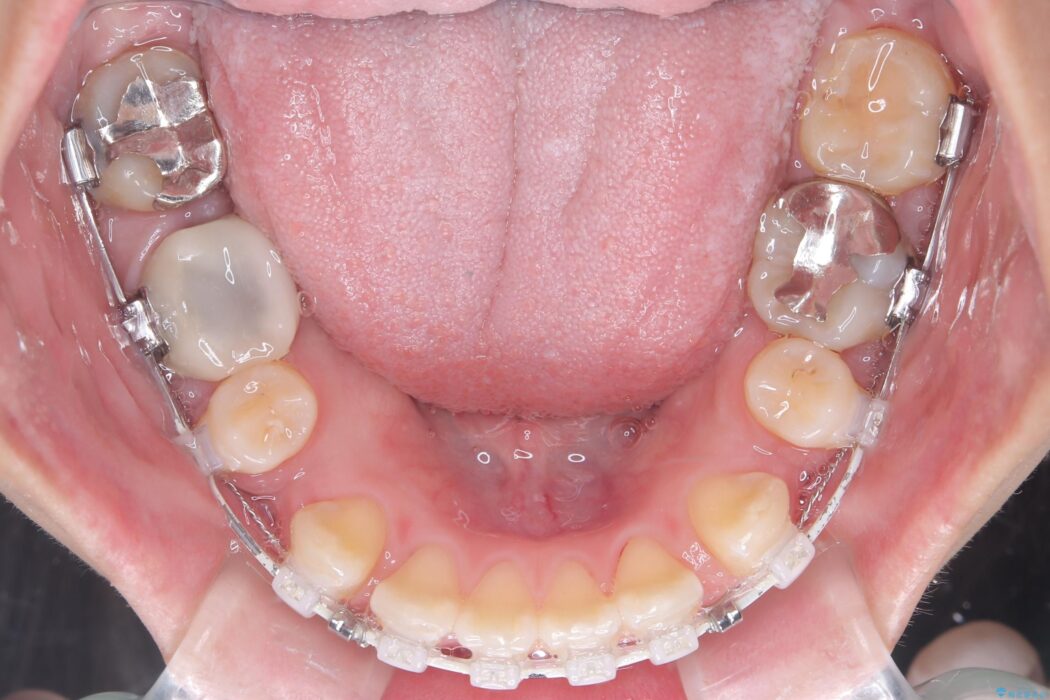

装置は人目を気にせず治療できるよう、上顎に裏側矯正、下顎に表側矯正を組み合わせたハーフリンガル矯正を提案しました。

装置には、上顎には目立たない裏側矯正(舌側矯正)を、下顎には透明な審美ブラケットを使用するハーフリンガル矯正を採用しました。抜歯によってできたスペースを最大限に活用し、前歯を効率よく後方へ移動。治療の結果、口元の突出感が大幅に解消され、Eライン(横顔の美しさの基準)も改善しました。人目を気にすることなく治療を完遂し、自信の持てる美しい横顔を獲得していただけました。